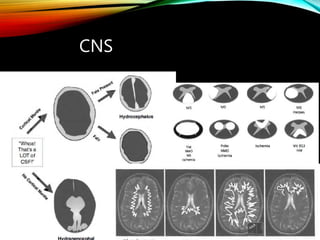

CNS